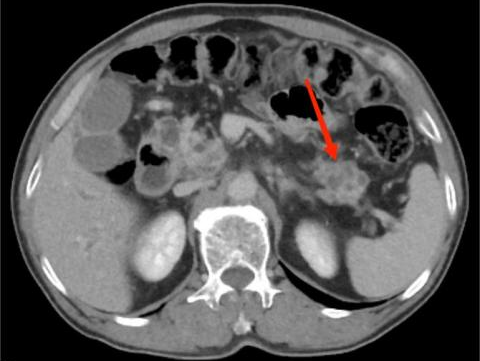

典型病例3:

女,62岁,无明显诱因出现腹痛,为左上腹痛,呈阵发性绞痛,程度剧烈。图A:平扫CT示胰尾部团块状稍低密度影(红箭头),与脾门分界不清;脾脏受侵,实质内见多发低密度影(黄箭头)。图B:增强扫描示胰尾部肿块呈轻度强化,脾脏多发低密度影呈轻度强化。